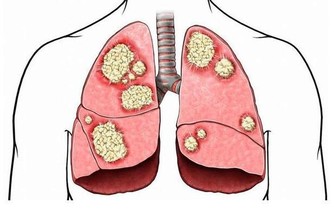

多發於唇、舌、牙齦和舌底,早期並無不適感,如果發生糜爛或潰瘍,會有強烈的疼痛感,但如果繼續惡化,斑塊突然快速增大增厚,這時就要特別小心了,可能是癌前病變的信號。